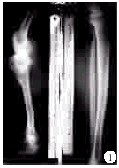

患者,男,19岁,因右胫骨血源性骨髓炎反复手术后严重肢体短缩畸形收入院。患者2岁时因寒战、高热,右小腿肿痛,溢脓在外院诊断为“右胫骨骨髓炎”,经4次手术治疗后控制感染。3岁多时又因“右胫骨感染后骨缺损”在外院行同侧腓骨移植代胫骨术,术后伤口再感染经换药后痊愈。随着年龄增长,右下肢短缩渐加剧,严重跛行,故来我院就诊。查体:右下肢跛行,胫前内侧全长15 cm×3 cm广泛贴骨瘢痕,较薄,无活动度。左足下垂15°僵直,内翻15°畸形,肢体长度测量髂前上棘至内踝,右侧63.5 cm,左侧84 cm,绝对长度短缩20.5 cm,其中大腿短缩2.5 cm,小腿短缩18 cm。功能性测量右下肢垫高15 cm后脊柱代偿性侧弯可以矫正,但骨盆呈部分固定代偿,右足垫高未能纠正骨盆倾斜,X线测量见图1。

图1 术前X线片